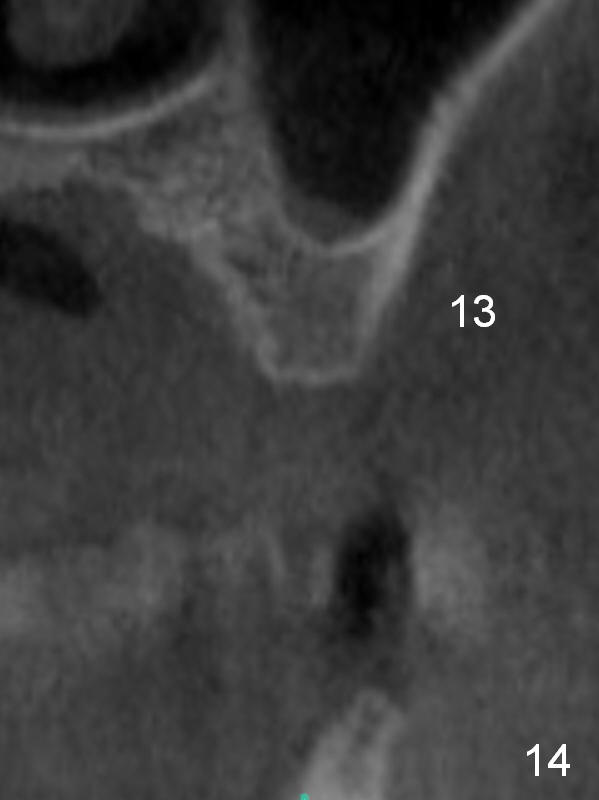

The ridge at #12 becomes a little bit wider and a 1-piece implant is placed palatal (Fig.13). The height of the alveolus and low bone density at #13 are limiting factors (Fig.14). The solutions will be sinus lift and bone condensation (Fig.15).